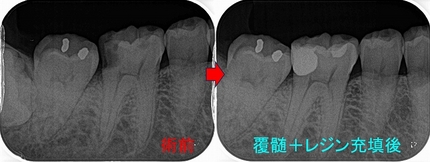

レントゲン

2026 EEdental NAY (1).jpg

第1大臼歯の黄色丸:C2~C3に及ぶ虫歯

第2大臼歯の赤丸:C4に近い虫歯

前に患者さんにも言いましたが、成功率を高くする為には

基本1つ次のステップの治療を行う事

つまり第1大臼歯は神経を取ってクラウン

第2大臼歯は抜歯

こうすることで将来トラブルの出る確率は多少減らせますが、

歯の寿命は確実に短くなりますし、咬みずらくなります。

ここが残りの人生を考えた際の選択になります。

短期予後を取るか!?それとも長い人生・将来的な事を考えた選択をするか!?

まず第一大臼歯はいつも通り

とりあえず神経を残す治療を行い、痛みが後で出てしまったら後で神経を取ると説明

2026 EEdental NAY (2).jpg

さて、この第2大臼歯・・・

縁下に大きく虫歯が広がっており、歯に穴を開けずに虫歯をきちんと取るのが超難度

保存をしても歯根破折、咬合から来る虫歯などが怖いのはあり、

将来起こるであろうこのリスクを下げるには抜歯も1つ

患者さんと話し合い、残す方向で治療を行いました。

2026 EEdental NAY (3).jpg

パフォレーションを起こさせないように虫歯を削るのに50分近くかかりましたが、

一応保存治療が行えました。

この先、数カ月様子を見て問題無ければ本歯を作らせてもらいます。